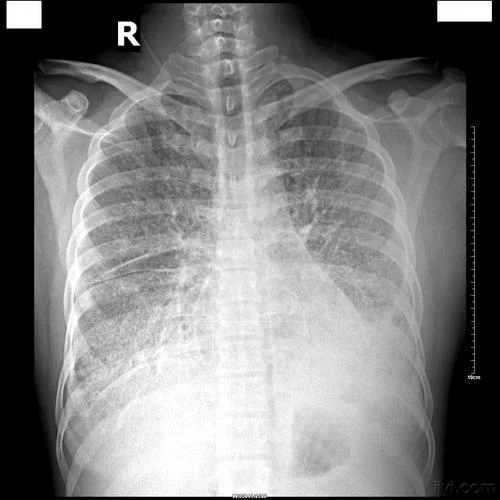

2. 定期体检:对高危人群进行定期胸片检查、肺功能检测等,以便早期发现病变,及早干预。